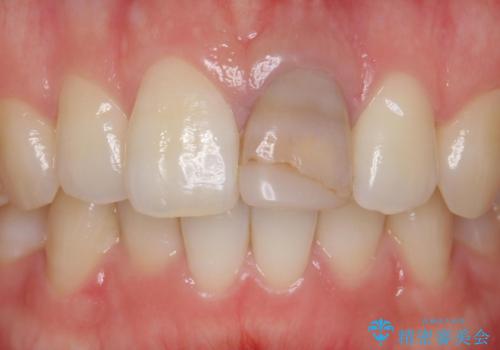

前歯が暗く変色 ジルコニアクラウンでの修復

- 前歯の変色を主訴に来院された患者様です。

より審美的な修復を行いたいとのことであったため、ジルコニアクラウンでの修復を行います。